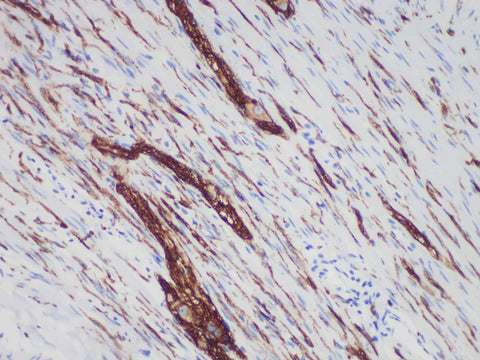

CD56 Monoclonal Antibody Synonyms CD56

Applications IHC-P

CD56 is a membrane glycoprotein that plays an important role in embryonic development and neural cell interaction. CD56 is widely found in neurons, glial cells, skeletal muscle cells, most types of neuroendocrine cells, and various epithelial cells. In the hematopoietic system, CD56 is a prototypical marker of NK cells and is also present in CD4+ and CD8+ T cell subsets. It is mainly used in the diagnosis and research of neuroectodermal tumors, small cell lung cancer and NK cell lymphoma.